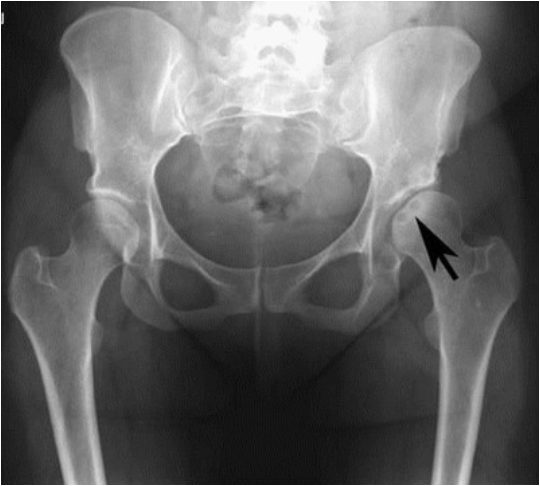

Как делают рентген тазобедренного сустава

Чтобы получить исчерпывающие сведения о состоянии пациента, ему делают обзорную рентгенограмму таза в прямой проекции. Проведение рентгенографии только одного сустава является ошибкой. Для полноценного анализа рентгенологу необходимо видеть снимки обоих ТБС. Часто выявить патологию ему помогает именно сравнение.

Вывих ТБС. Головка бедренной кости смещена и выходит на пределы вертлужной впадины.

Перелом. Имеет вид линии или щели. Чаще всего располагается в области шейки бедренной кости.